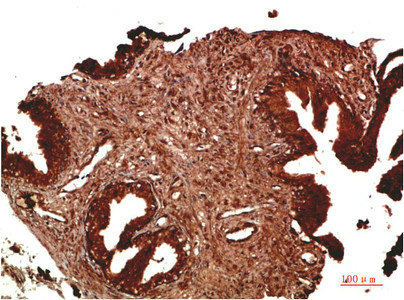

Immunohistochemical analysis of paraffin-embedded Human Prostate Carcinoma Tissue using ATM Rabbit pAb diluted at 1:200.